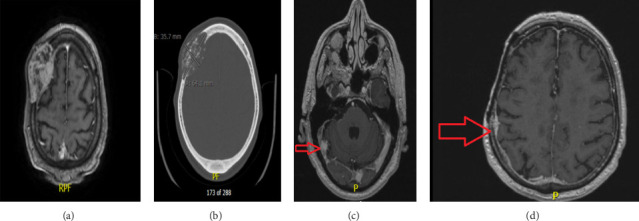

背景:从软组织和骨肉瘤转移的脑肿瘤并不常见。脑转移性肉瘤是一种侵袭性很强的疾病,预后差。关于骨肉瘤脑转移的治疗尚无共识。临床表现:患者60岁,右撇子男性,表现为右额部头皮肿胀,硬稠度。经检查,他肿胀处有疼痛和压痛。神经系统检查正常。检查:最初的CTH显示右额颅骨病变具有特征性的扩张和晒斑外观,并伴有一定程度的皮质破坏。脑MRI示颅骨骨肉瘤征象。治疗方法:行肿瘤次全切除术。他被诊断为颅骨高度软骨母细胞瘤样骨肉瘤。随后,他接受了三个周期的阿霉素和顺铂新辅助化疗。一年后,他接受了进一步的手术干预,并使用补片和头皮重建进行了额外的颅骨切除术和重建。随访:MRI脑造影显示右侧横窦及其他脑远区远处转移,原发手术后6个月行伽玛刀放射治疗。结论:颅骨原发性骨肉瘤是一种罕见的疾病。颅骨骨肉瘤脑转移是一个具有挑战性的临床情况,需要多学科的治疗方法,包括神经外科、整形外科、化疗和放射外科。

Background: Cerebral metastases from soft tissue and bone sarcoma are uncommon. Metastatic sarcoma of the brain is a highly aggressive disease with a poor prognosis. There is no consensus regarding the management of cerebral metastases from bone sarcomas. Clinical Presentation: The patient is a 60-year-old, right-handed male, who presented with a right frontal scalp swelling that was hard in consistency. On examination, he had pain and tenderness over the swelling. The neurological examination was normal. Investigations: Initial CTH revealed a right frontal skull lesion with characteristic expansion and sunburst appearance with a degree of cortical destruction. MRI brain with contrast showed features suggestive of skull osteosarcoma. Management: He underwent a subtotal tumor resection. He was diagnosed with high-grade chondroblastoma-like osteosarcoma of the skull. Subsequently, he received three cycles of neoadjuvant chemotherapy in the form of Adriamycin and cisplatin. One year later, he underwent further surgical intervention with an additional skull resection and reconstruction using mesh and scalp reconstruction. Follow-Up: MRI brain with contrast showed a distant metastasis in the right transverse sinus and other distant brain areas and were treated with Gamma Knife radiosurgery (GKRS) 6 months after the primary surgery. Conclusion: Skull calvarium primary osteosarcoma is a rare pathology. Cerebral metastasis from skull bone osteosarcoma is a challenging clinical situation that requires a multidisciplinary therapeutic approach that includes neurosurgery, plastic surgery, chemotherapy, and radiosurgery.